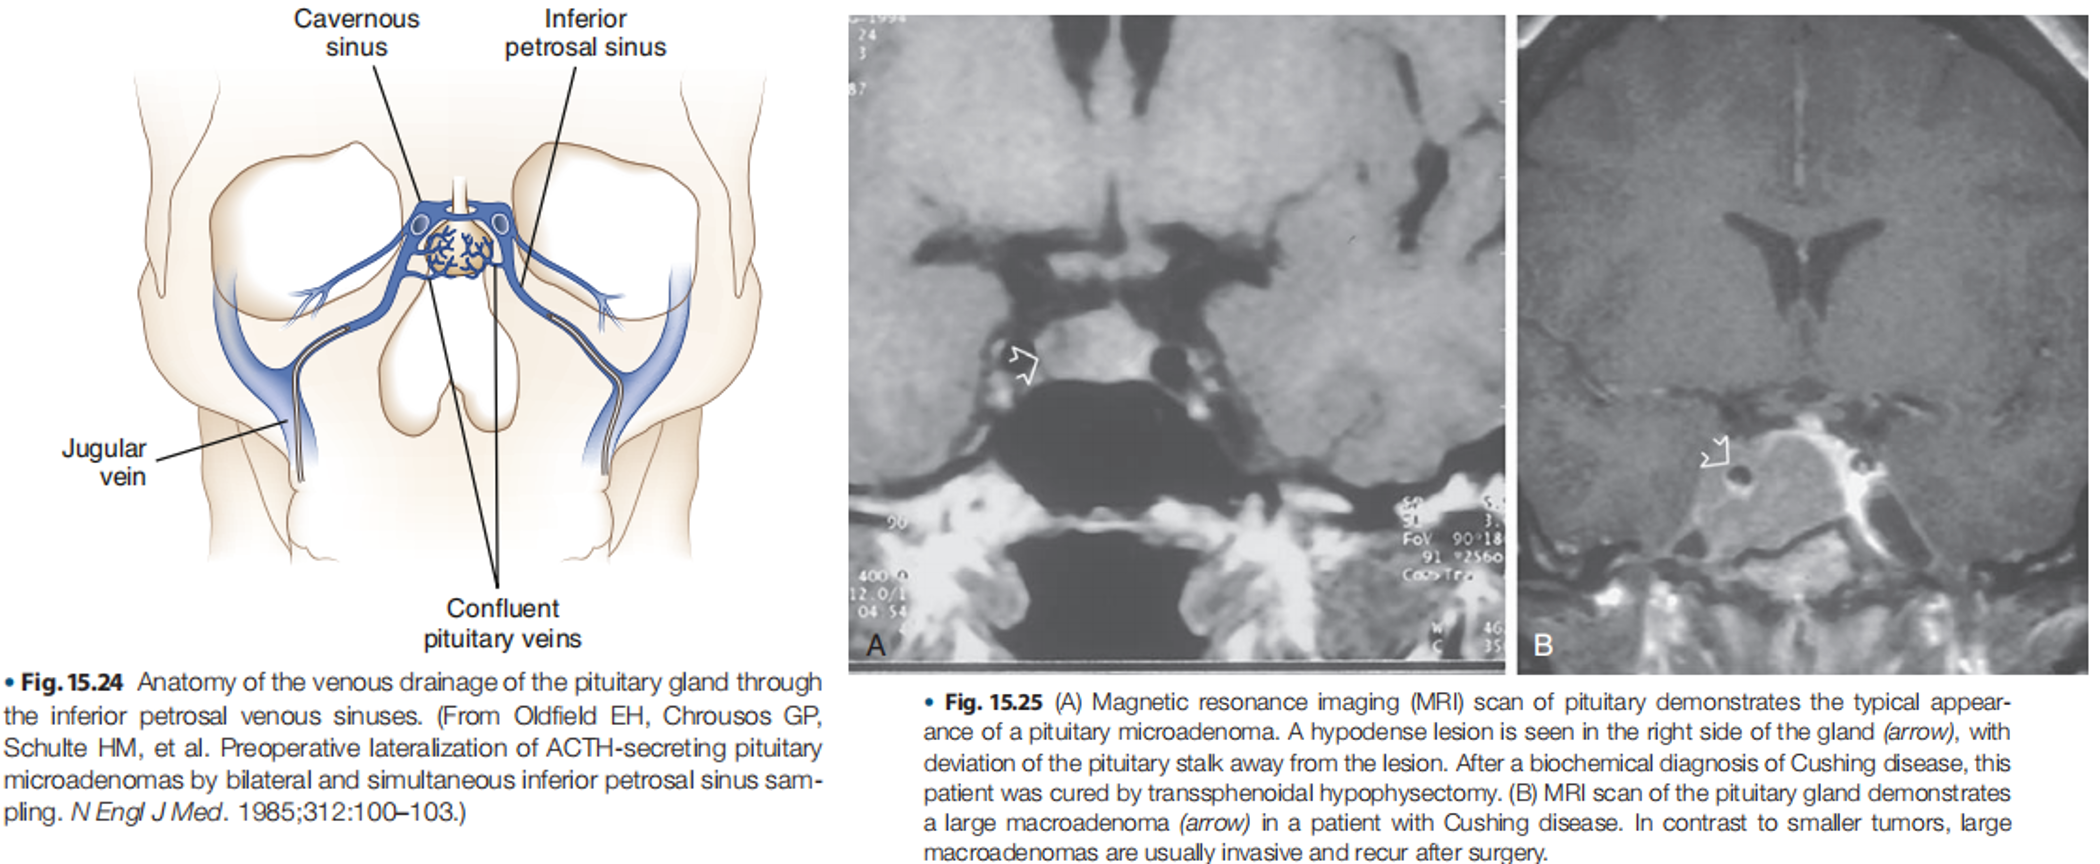

- Inferior Petrosal Sinus Sampling (IPSS): The gold standard for differentiating pituitary from ectopic ACTH secretion.

- Gold Standard: For differentiating pituitary (Cushing’s Disease) from ectopic ACTH secretion.

- Procedure: Catheters are placed in the inferior petrosal sinuses (which drain the pituitary gland) and a peripheral vein. ACTH levels are measured in both locations after administering corticotropin-releasing factor (CRF).

- Interpretation: A central-to-peripheral ACTH ratio helps determine the source of ACTH.

- Invasive: Only performed at specialized centers.

Current Practice: MRI of the pituitary and/or IPSS are preferred for differentiating pituitary from ectopic ACTH secretion.

- Pituitary Source (Cushing’s Disease): Transsphenoidal surgery to remove the pituitary adenoma.